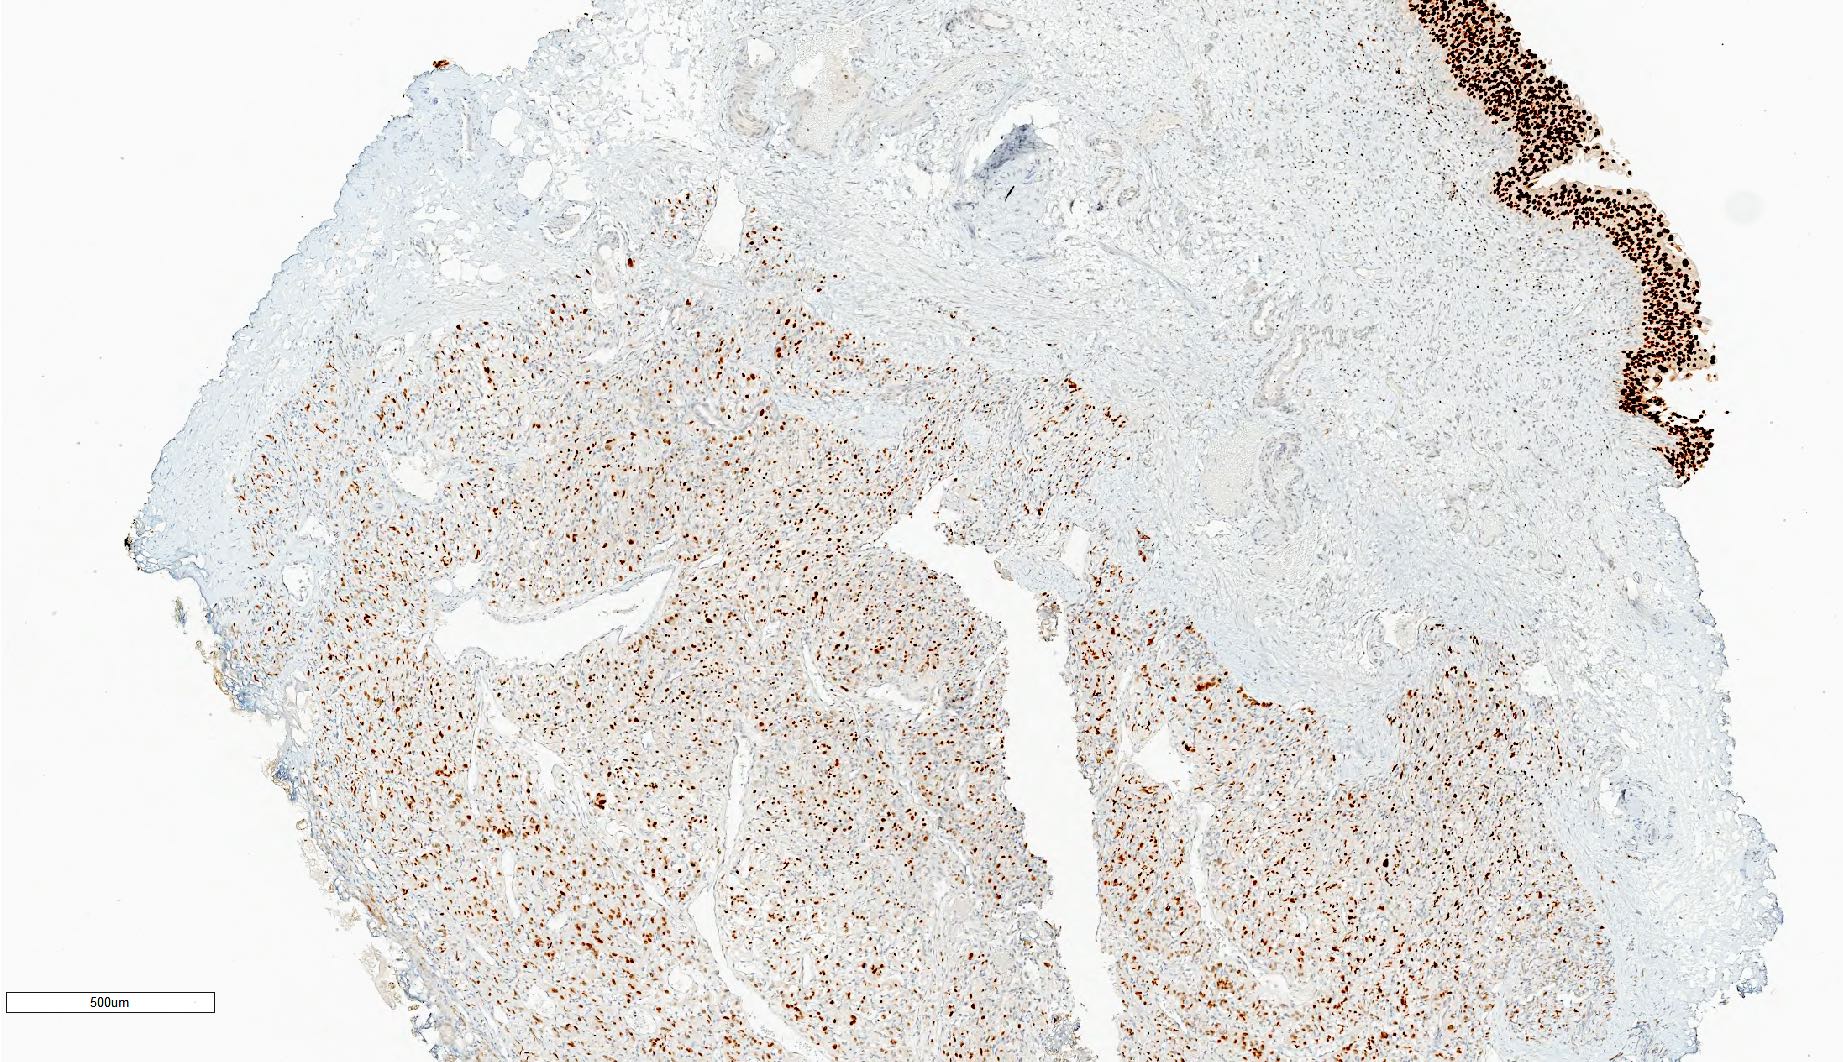

- SDHB germline mutation is the strongest genetic prognosticator of poor outcomes; SDHB immunohistochemistry is routinely used for its identification

- Grading system for adrenal pheochromocytoma and paraganglioma (GAPP), with unfavorable factors being large and irregular cell nest, pseudorosette (even focal), comedo type necrosis, moderate to high cellularity, Ki67 labeling index > 1 - 3%, vascular or capsular invasion and noradrenergic type (Endocr Relat Cancer 2014;21:405)

- Modified GAPP: based on the same prognostic factors as GAPP with the addition of SDHB loss on IHC (PLoS One 2017;12:e0187398)

- COPPS (composite pheochromocytoma / paraganglioma prognostic score), with unfavorable factors being focal or confluent necrosis, PS100 loss, vascular invasion, SDHB loss, tumor size > 7 cm, capsular invasion, increased mitotic figures and MCM6 (minichromosome maintenance) > 30% (Virchows Arch 2019;474:721)

Contributed by Theodorus H. van der Kwast, M.D., Ph.D., Michelle R. Downes, M.D., Debra L. Zynger, M.D. and David Cohen, M.B.B.Ch., M.D.

- SDHB loss (absence of granular cytoplasmic labeling) if SDHB mutation

- SDHA loss (absence of strong diffuse granular cytoplasmic labeling) if SDHA mutation

- Paraganglioma, SDHB staining intact (see comment)

- Comment: The risk of malignancy in these lesions is estimated at 5 - 15% of cases. Malignant behavior cannot be predicted based on morphology alone and relies on the identification of metastases. Tumors associated with SDHB mutations (loss of SDHB staining) are reported to have an increased risk of metastases.

- Microscopic description: This specimen shows an unencapsulated, monomorphous population of round tumor cells in a nested / zellballen pattern with delicate vascular septa and intervening extravasated red blood cells. It predominantly involves the lamina propria of the bladder but in 1 tissue piece clearly involves muscularis propria. The tumor cells have abundant amphophilic cytoplasm and vesicular chromatin with occasional small nucleoli. There is no necrosis, diffuse growth pattern or vascular space invasion identified. The mitotic count is (maximally) 1/10 high power fields. Immunohistochemistry shows the tumor cells to be positive for GATA3 with strong and diffuse expression of synaptophysin and chromogranin, as well as retention of SDHB staining. The tumor cells are negative for AE1 / AE3, HMWK and p63. The Ki67 proliferation index is < 1%. S100 shows faint nuclear and cytoplasmic staining with occasional sustentacular cells identified.

- Microscopic description: Sections show unremarkable surface urothelium with a lesion in the deep lamina propria comprised of large eosinophilic cells with hyperchromatic, focally enlarged nuclei with occasional intranuclear inclusions. A fine vascular plexus is identified in some areas. Necrosis and hemorrhage are not identified. Mitotic rate = 1/10 high power fields (field of view [FOV] = 0.55 mm). The lesion extends to the cauterized base of the specimen. Immunostains confirm the lesion expresses synaptophysin, chromogranin and GATA3. SDHB is retained. AE1 / AE3, CD45, p63 and NKX3.1 are negative.

D. SDHB. SDHB germline mutation is the strongest genetic risk factor for metastatic disease. The diagnosis of SDHB related paraganglioma can be supported by the loss of SDHB immunoreactivity in the tumor cells. Answer A is incorrect because while the presence of BRAF mutation has been described in a small subset of cases, it has not been proven to be associated with an increased risk for metastatic disease. Answer C is incorrect because while TP53 has been suggested to be a disease modifying gene, its association with a more aggressive disease behavior requires further studies. Answer B is incorrect because FH is a novel genetic risk factor for tumor aggressiveness but it is not the strongest genetic prognosticator of poor outcomes in paragangliomas.